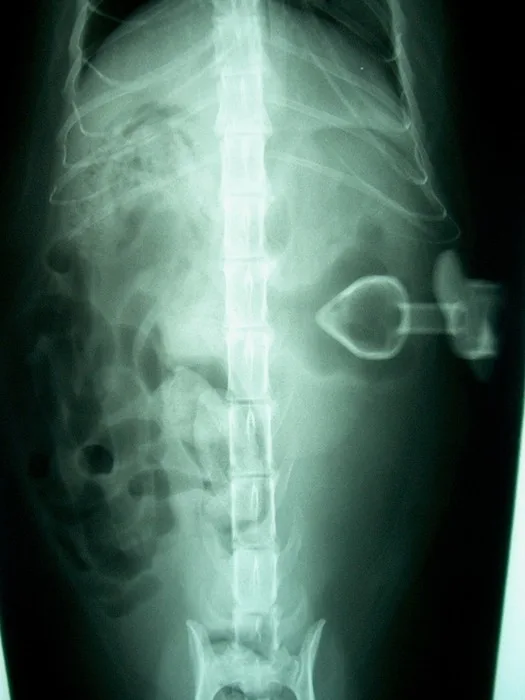

• Figures 4a & 4b. Ventrodorsal and lateral radiographs of percutaneously placed gastrostomy tube showing that the intraabdominal portion of the tube is not contained within the stomach. A number of small, irregularly shaped air bubbles are visible in this region (arrows). There is a mild decrease in midabdominal peritoneal detail that may be caused by the overlying wet hair or peritoneal fluid. (Courtesy of Dr. Eric Ferrell, University of Florida)